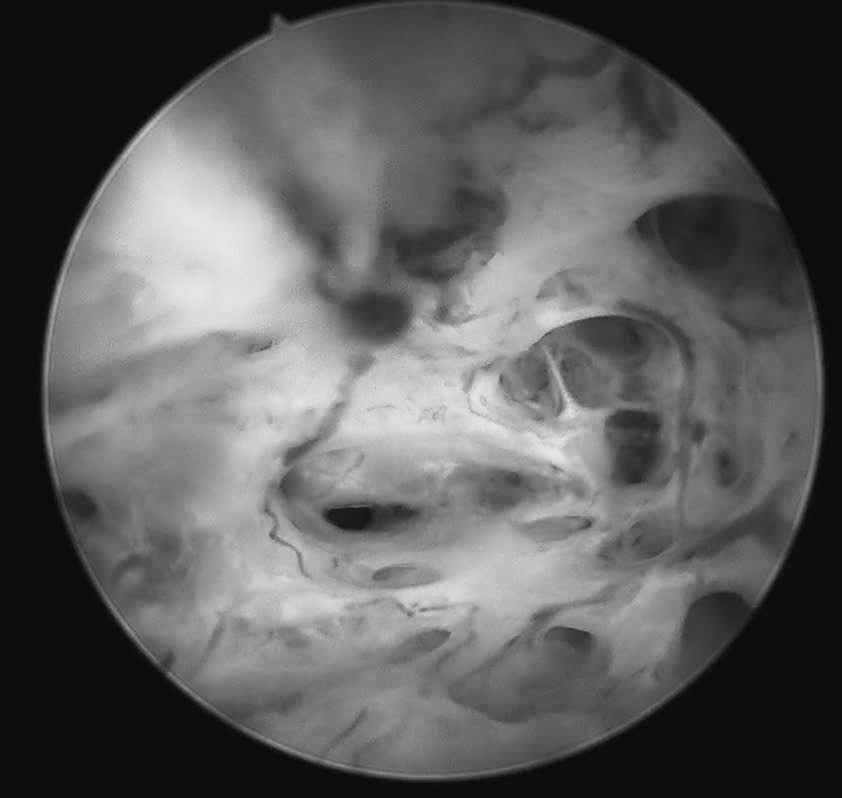

Quá trình soi diễn ra an toàn, nhẹ nhàng. Bệnh nhân hoàn toàn tỉnh táo và có thể quan sát trực tiếp hình ảnh buồng tử cung trên màn hình với hình ảnh niêm mạc nham nhở, tăng sinh không đồng đều, nhiều mạch máu bất thường, những dấu hiệu gợi ý tổn thương ác tính. Mẫu sinh thiết được lấy ngay trong quá trình soi để làm xét nghiệm mô bệnh học.

Năm ngày sau ca thủ thuật do ThS.BSCKII Nguyễn Biên Thùy, Trưởng khoa Khám Phụ khoa Tự nguyện trực tiếp thực hiện, kết quả xét nghiệm được trả về với thông tin không ai mong muốn. Nữ bệnh nhân trẻ được chẩn đoán mắc "ung thư niêm mạc tử cung".